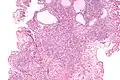

| Micrograph of a nephrogenic adenoma. H&E stain. | |

Nephrogenic adenomas are diagnosed under the microscope by pathologists. Microscopically the tumor shows closely packed small tubular structures in edematous stroma. The tubules show considerable variation in size and shape resembling convoluted tubules of the kidney. The single layer of cells lining the tubules are cuboidal with a scant to moderate amount of cytoplasm. In some areas they may have a hobnail appearance. [2]

Low mag -